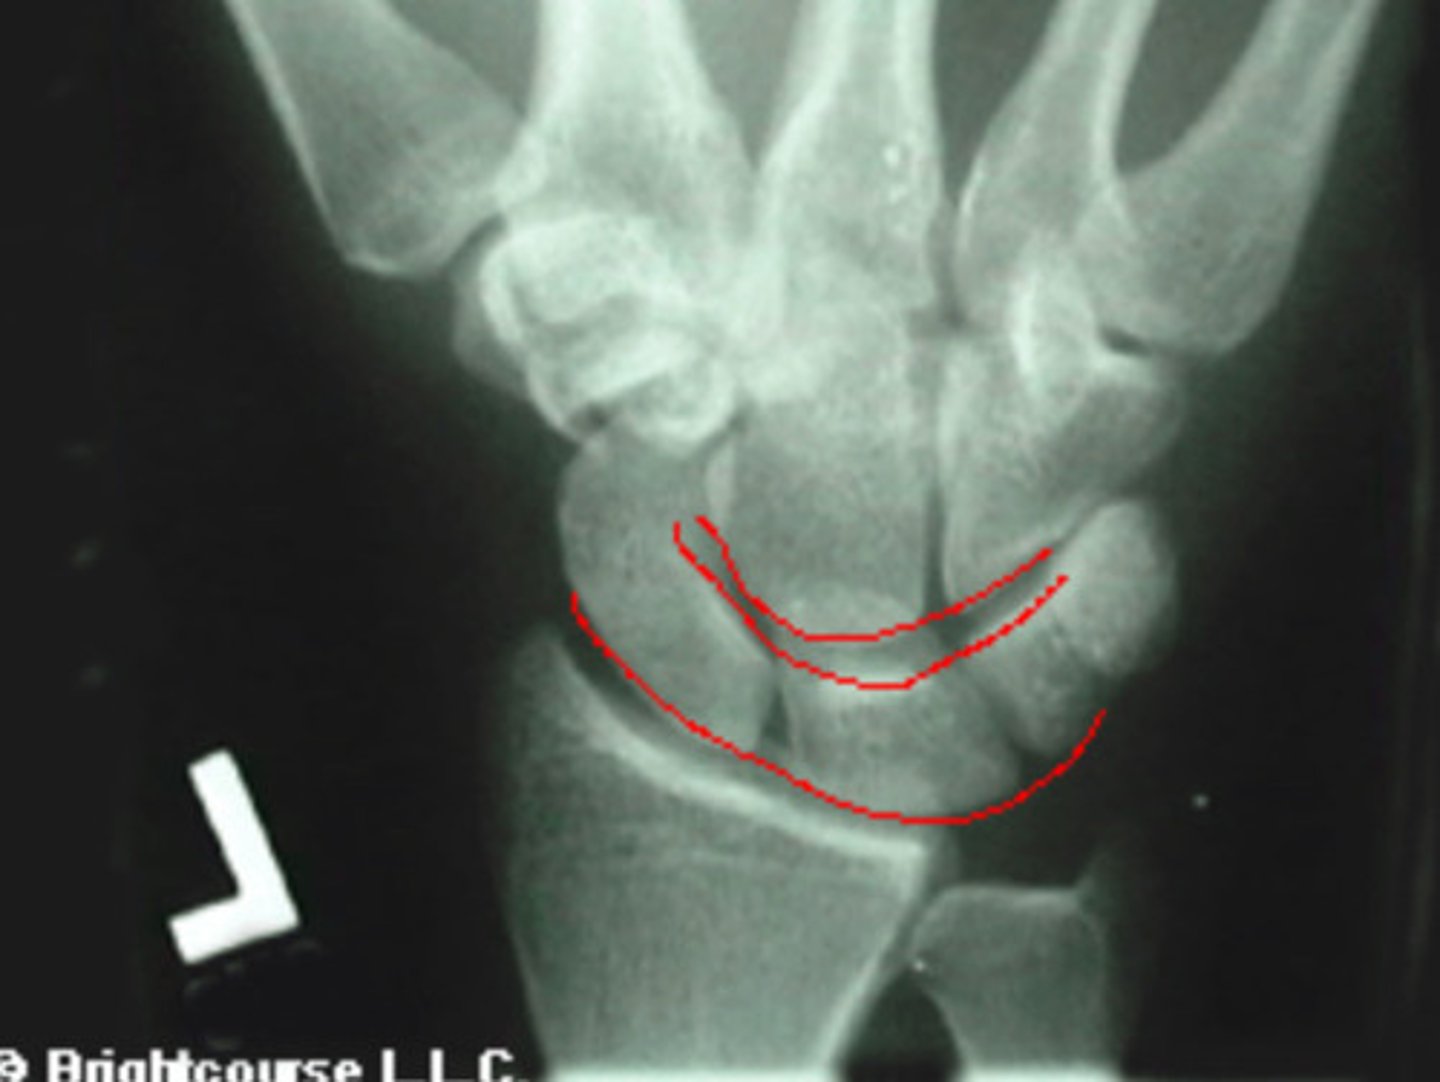

3 arcs of carpal alignment

What is being assessed in this image?